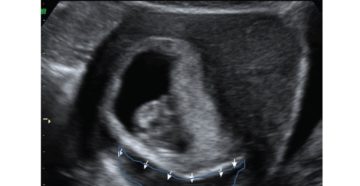

Отслойка плодного яйца на ранних сроках беременности: деформация гематома Плодное яйцо обнаруживают на УЗИ в…